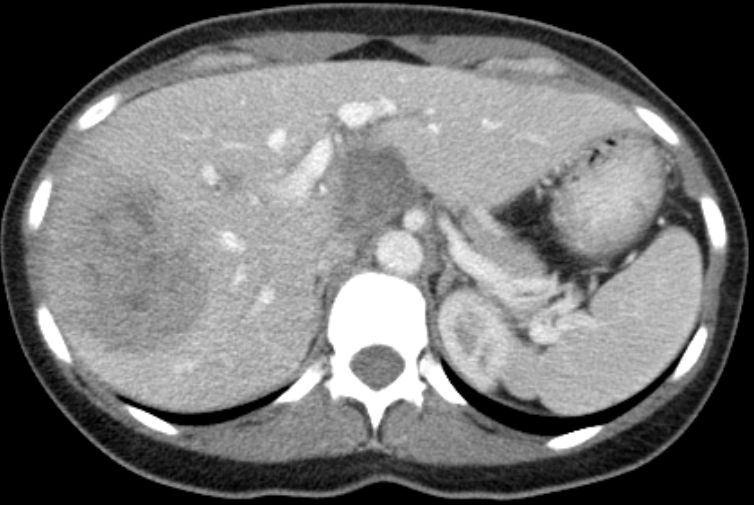

39-jährige Frau mit einem primär hepatisch metastasierten Transversum-Karzinom. Histologisch gering differenziertes Adenokarzinom ras-Wildtyp. Das CT zeigt eine große Metastase im rechten Leberlappen und eine Metastase im Lobus caudatus. Letztere ist schwer zu resezierten und sollte in einem Zentrum operiert werden.